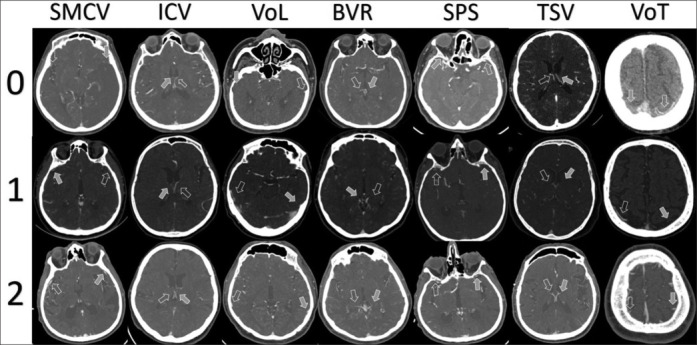

Patients and methods: A total of 130 patients (mean age: 71 years; 73 females) with acute middle cerebral artery M1/M2 segment or terminal internal carotid artery occlusion treated solely with IV-tPA were analyzed. Regional leptomeningeal score (rLMC) was used for cerebral arterial collateral scoring, and the cortical vein opacification score (COVES) and modified Prognostic Evaluation based on Cortical vein score difference In Stroke (PRECISE) superficial and deep scores were used for venous outflow profile. Exploratory logistic models for response to IV-tPA [positive response: National Institutes of Health Stroke Scale (NIHSS) decrease 4 (or decrease to 0) at 24 h; dramatic response: NIHSS decrease ≥8 (or decrease to 0 or 1)], functional outcome (modified Rankin's score 0-1 as "excellent" and 0-2 "good") and tPA-associated hemorrhagic transformation were constructed.

Abstract Image